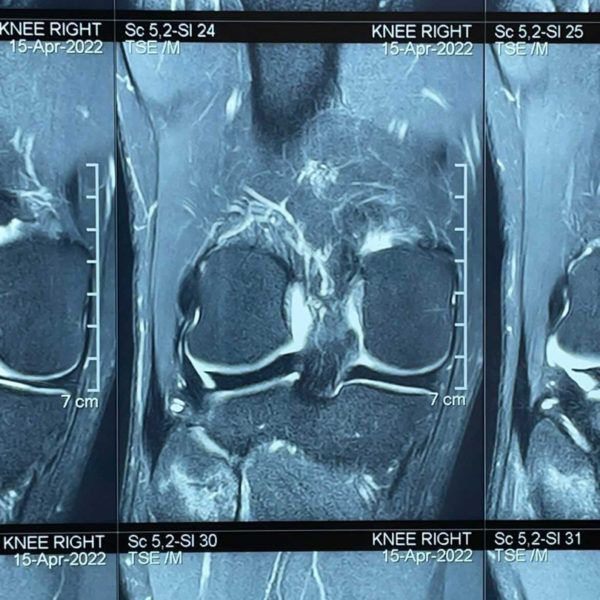

An x-ray at the clinic revealed no injuries. I insisted something was not right so the orthopedic surgeon recommended an MRI. Three hundred dollars later, the results revealed a fracture in the head of my fibula. I returned to the Nepali surgeon with the results and after hearing him say, “Your expedition is over,” I politely looked him in the eye and said, “Sir, I’ve spoken to my team and they’ve explained to me that it’s a non-weight bearing bone. Plus, I’ve been to the summit of Everest four times. Given it’s fractured just the right way, why don’t we focus on a solution rather than the problem?” He looked at me, incredulous, but nodded.